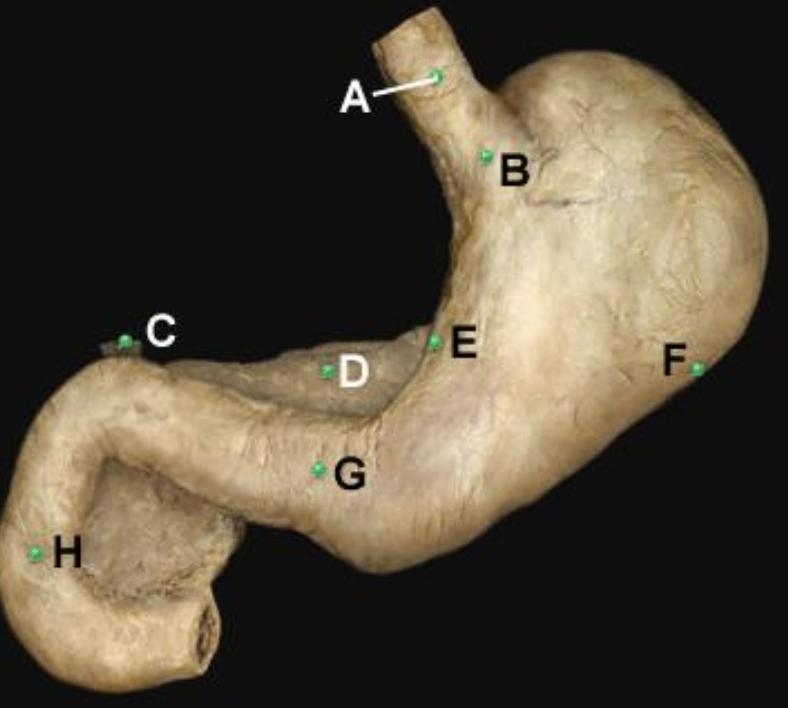

Part A?

esophagus

Part B?

cardia of stomach

Part C?

Bile duct

Part D?

pancreas

Part E?

lesser curvature of stomach

Part F?

greater curvature of stomach